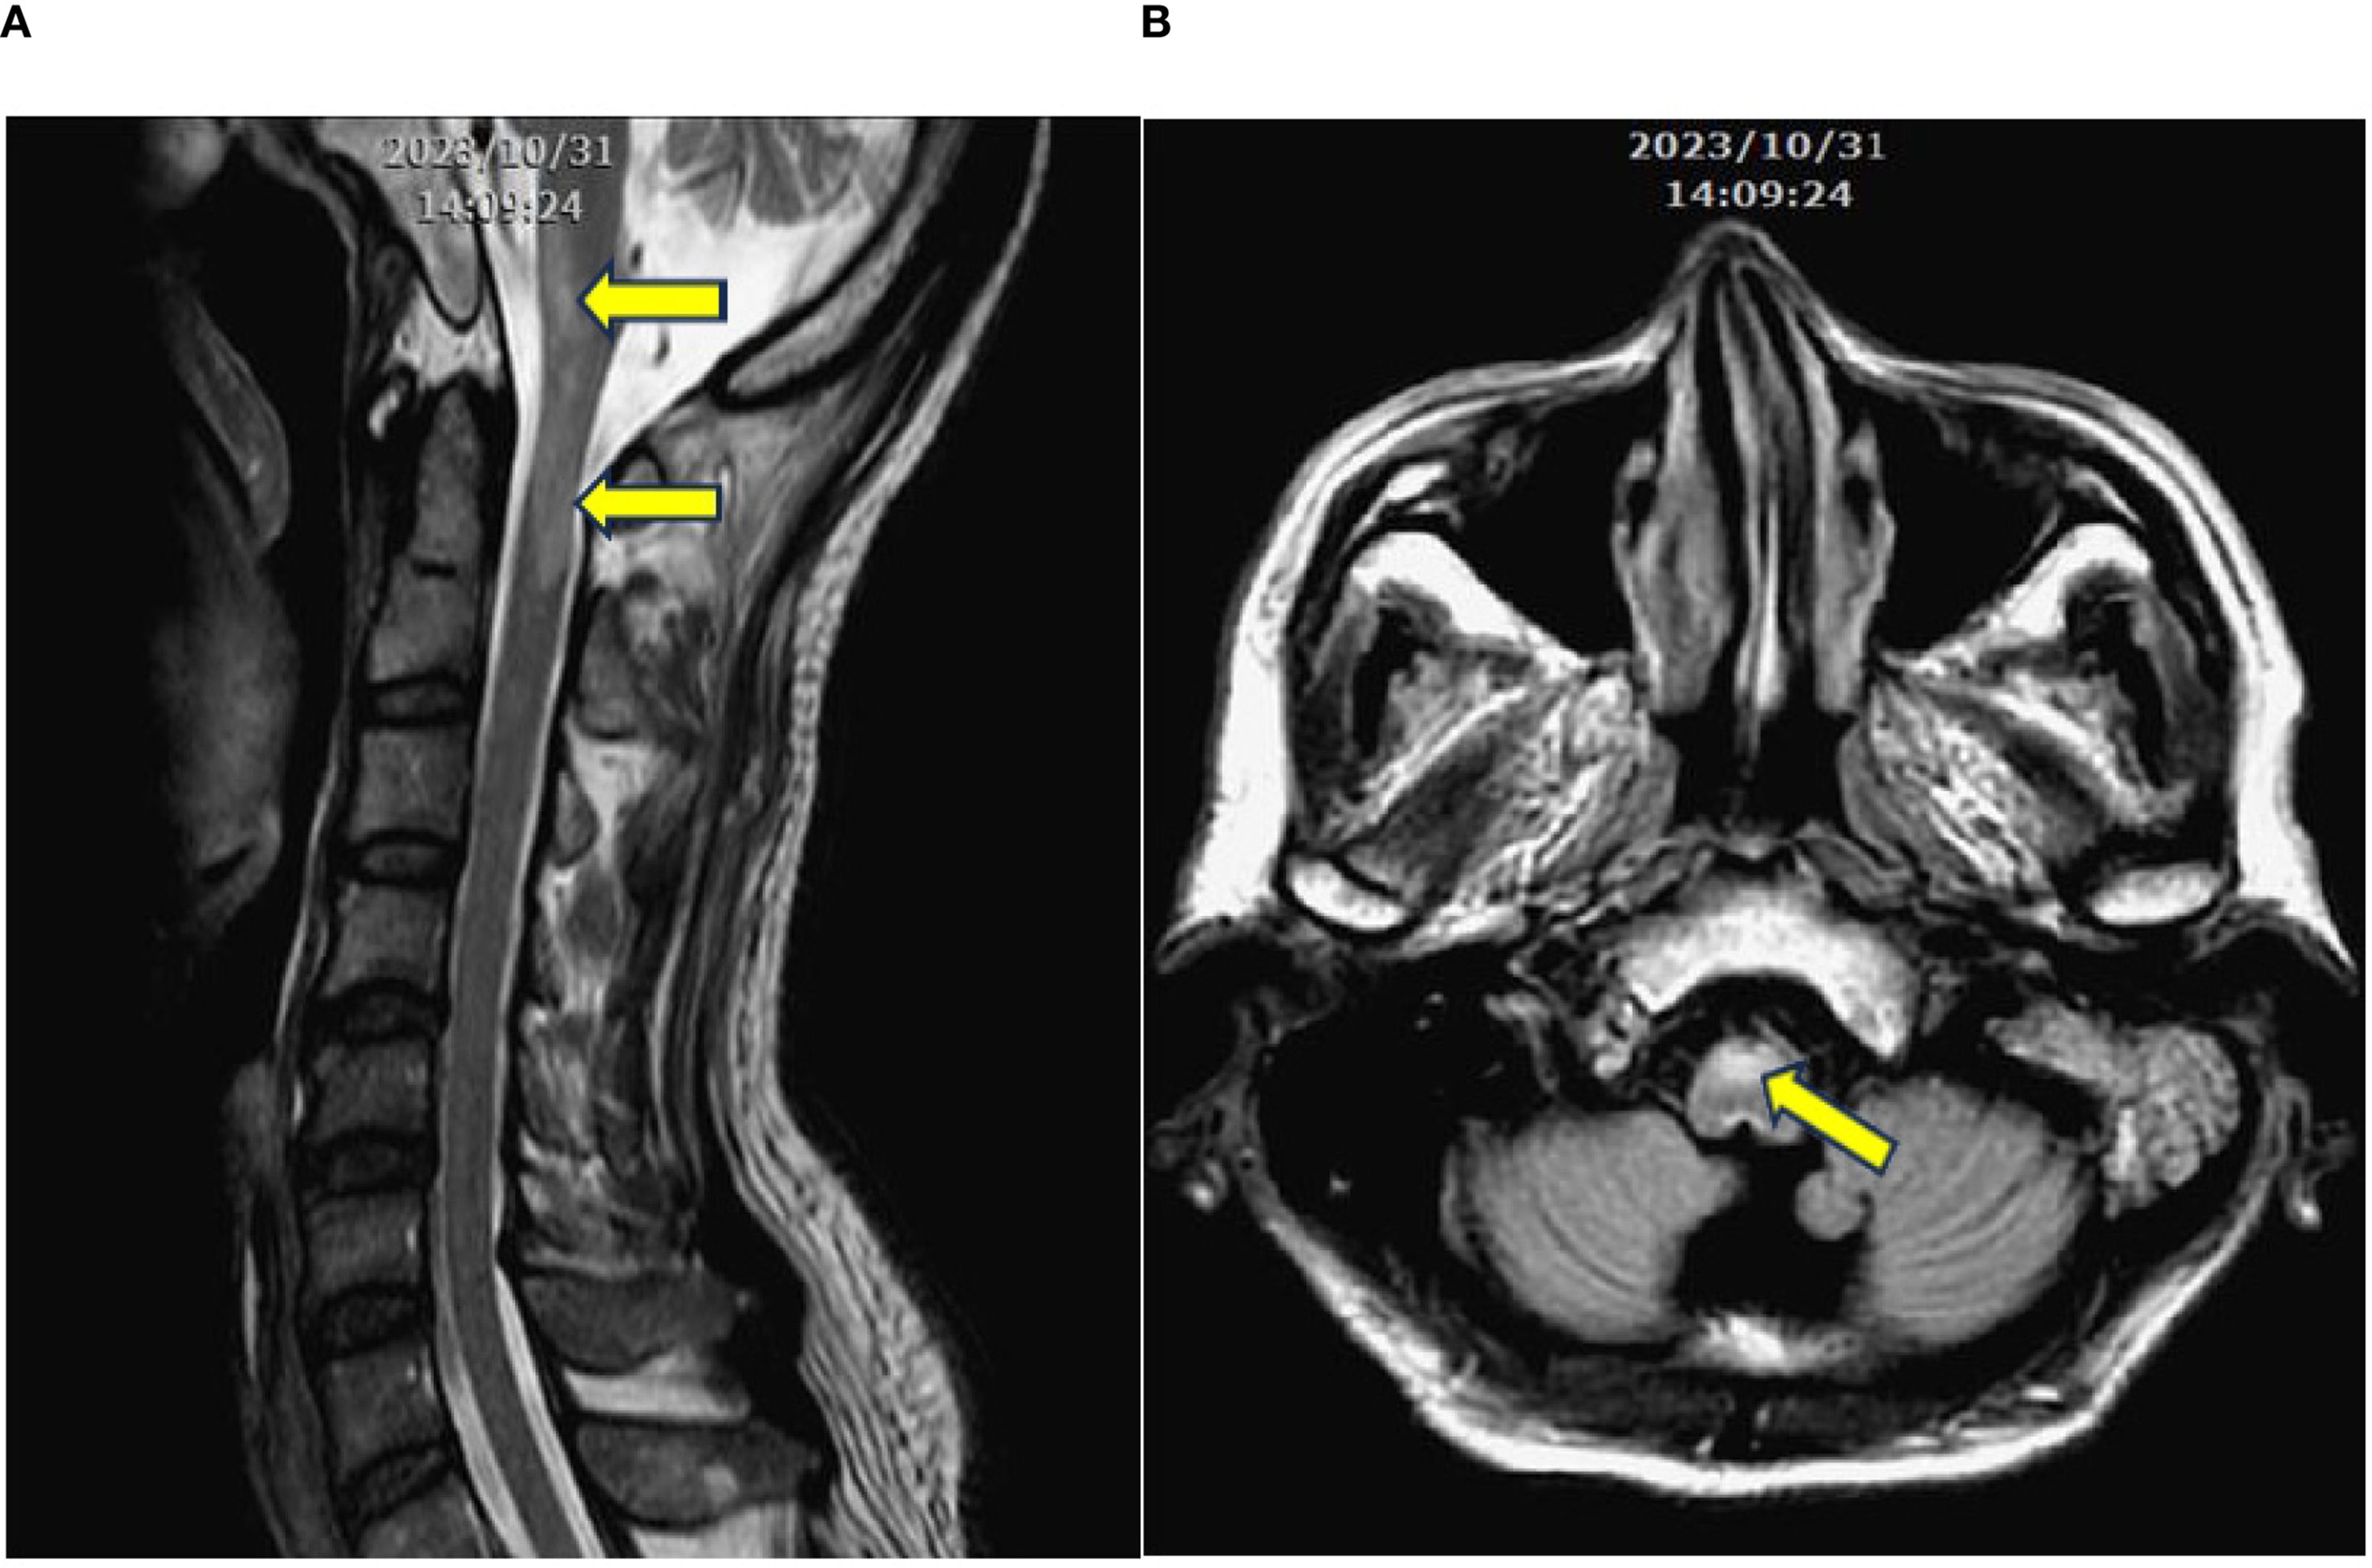

After stabilizing medical conditions, he was transferred to rehabilitation ward with decreased muscle power of 4 limbs with 3 scores in manual muscle test (MMT), fair trunk stability and sitting balance, disability to stand up from sitting, near totally dependent ADL, and dysphagia. Rehabilitation program was arranged, including muscle strengthening and endurance training for 4 limbs weakness, balance and trunk stability training, ambulation training, functional training, ADL training, and swallowing training for dysphagia. Video-fluoroscopy of swallowing, VFSS, was performed, revealing weak pharyngeal contraction with contrast retention in the valleculae and piriform sinuses after swallowing, accompanied with laryngeal penetration (Figure 2). Swallowing training with pharyngeal muscles strengthening and swallowing technique was performed for dysphagia and laryngeal penetration.

Figure 2. Videofluroscopic swallowing study. Weak pharyngeal contraction with evident contrast retention in the valleculae and piriform sinuses after swallowing, accompanied with laryngeal penetration (arrows).

Following stabilization, the patient received a comprehensive inpatient rehabilitation program, including muscle strengthening, balance and ambulation training, functional task training, and swallowing training based on VFSS findings.